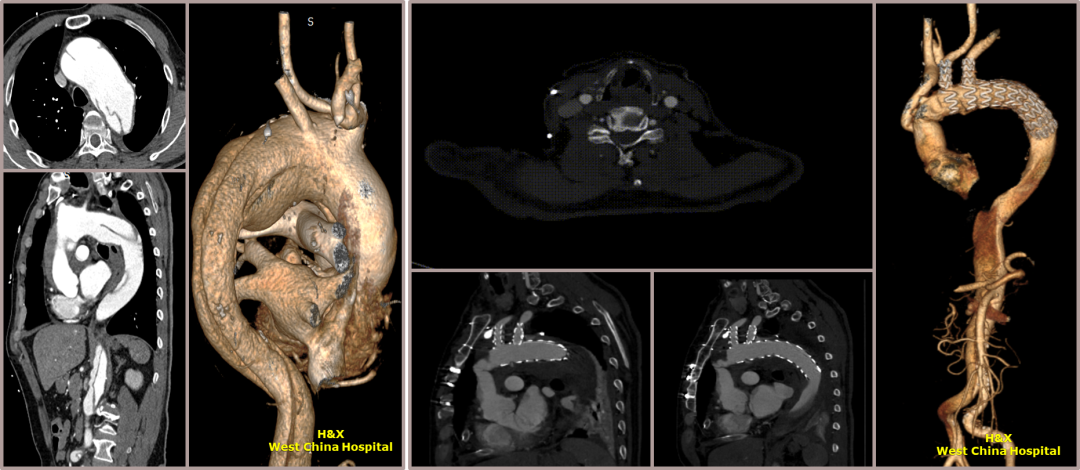

★ Case 1

男性,42岁,胸痛3天;

既往史:高血压,规律服用降压药物;

手术史:10年前外院行主动脉腔内修复+左颈总及左锁骨下烟囱支架植入;

夹层动脉瘤CTA:逆撕A型主动脉夹层,升主动脉及无名动脉见夹层累及,左颈总及左锁骨下动脉烟囱支架。

术前影像

术后影像

术后CTA